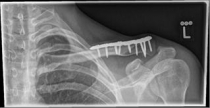

Acromioclavicular (lateral clavicular fracture), should be treated surgically, as a conservative therapy often leads to the formation of a so-called pseudarthrosis. Various implants are available, such as the hook plate and an anatomically preformed angular stable lateral clavicle plate.

Images: A lateral clavicle fracture was treated with a hook plate. The hook is fixed under the acromioclavicular, while screws anchor the plate in the collarbone.